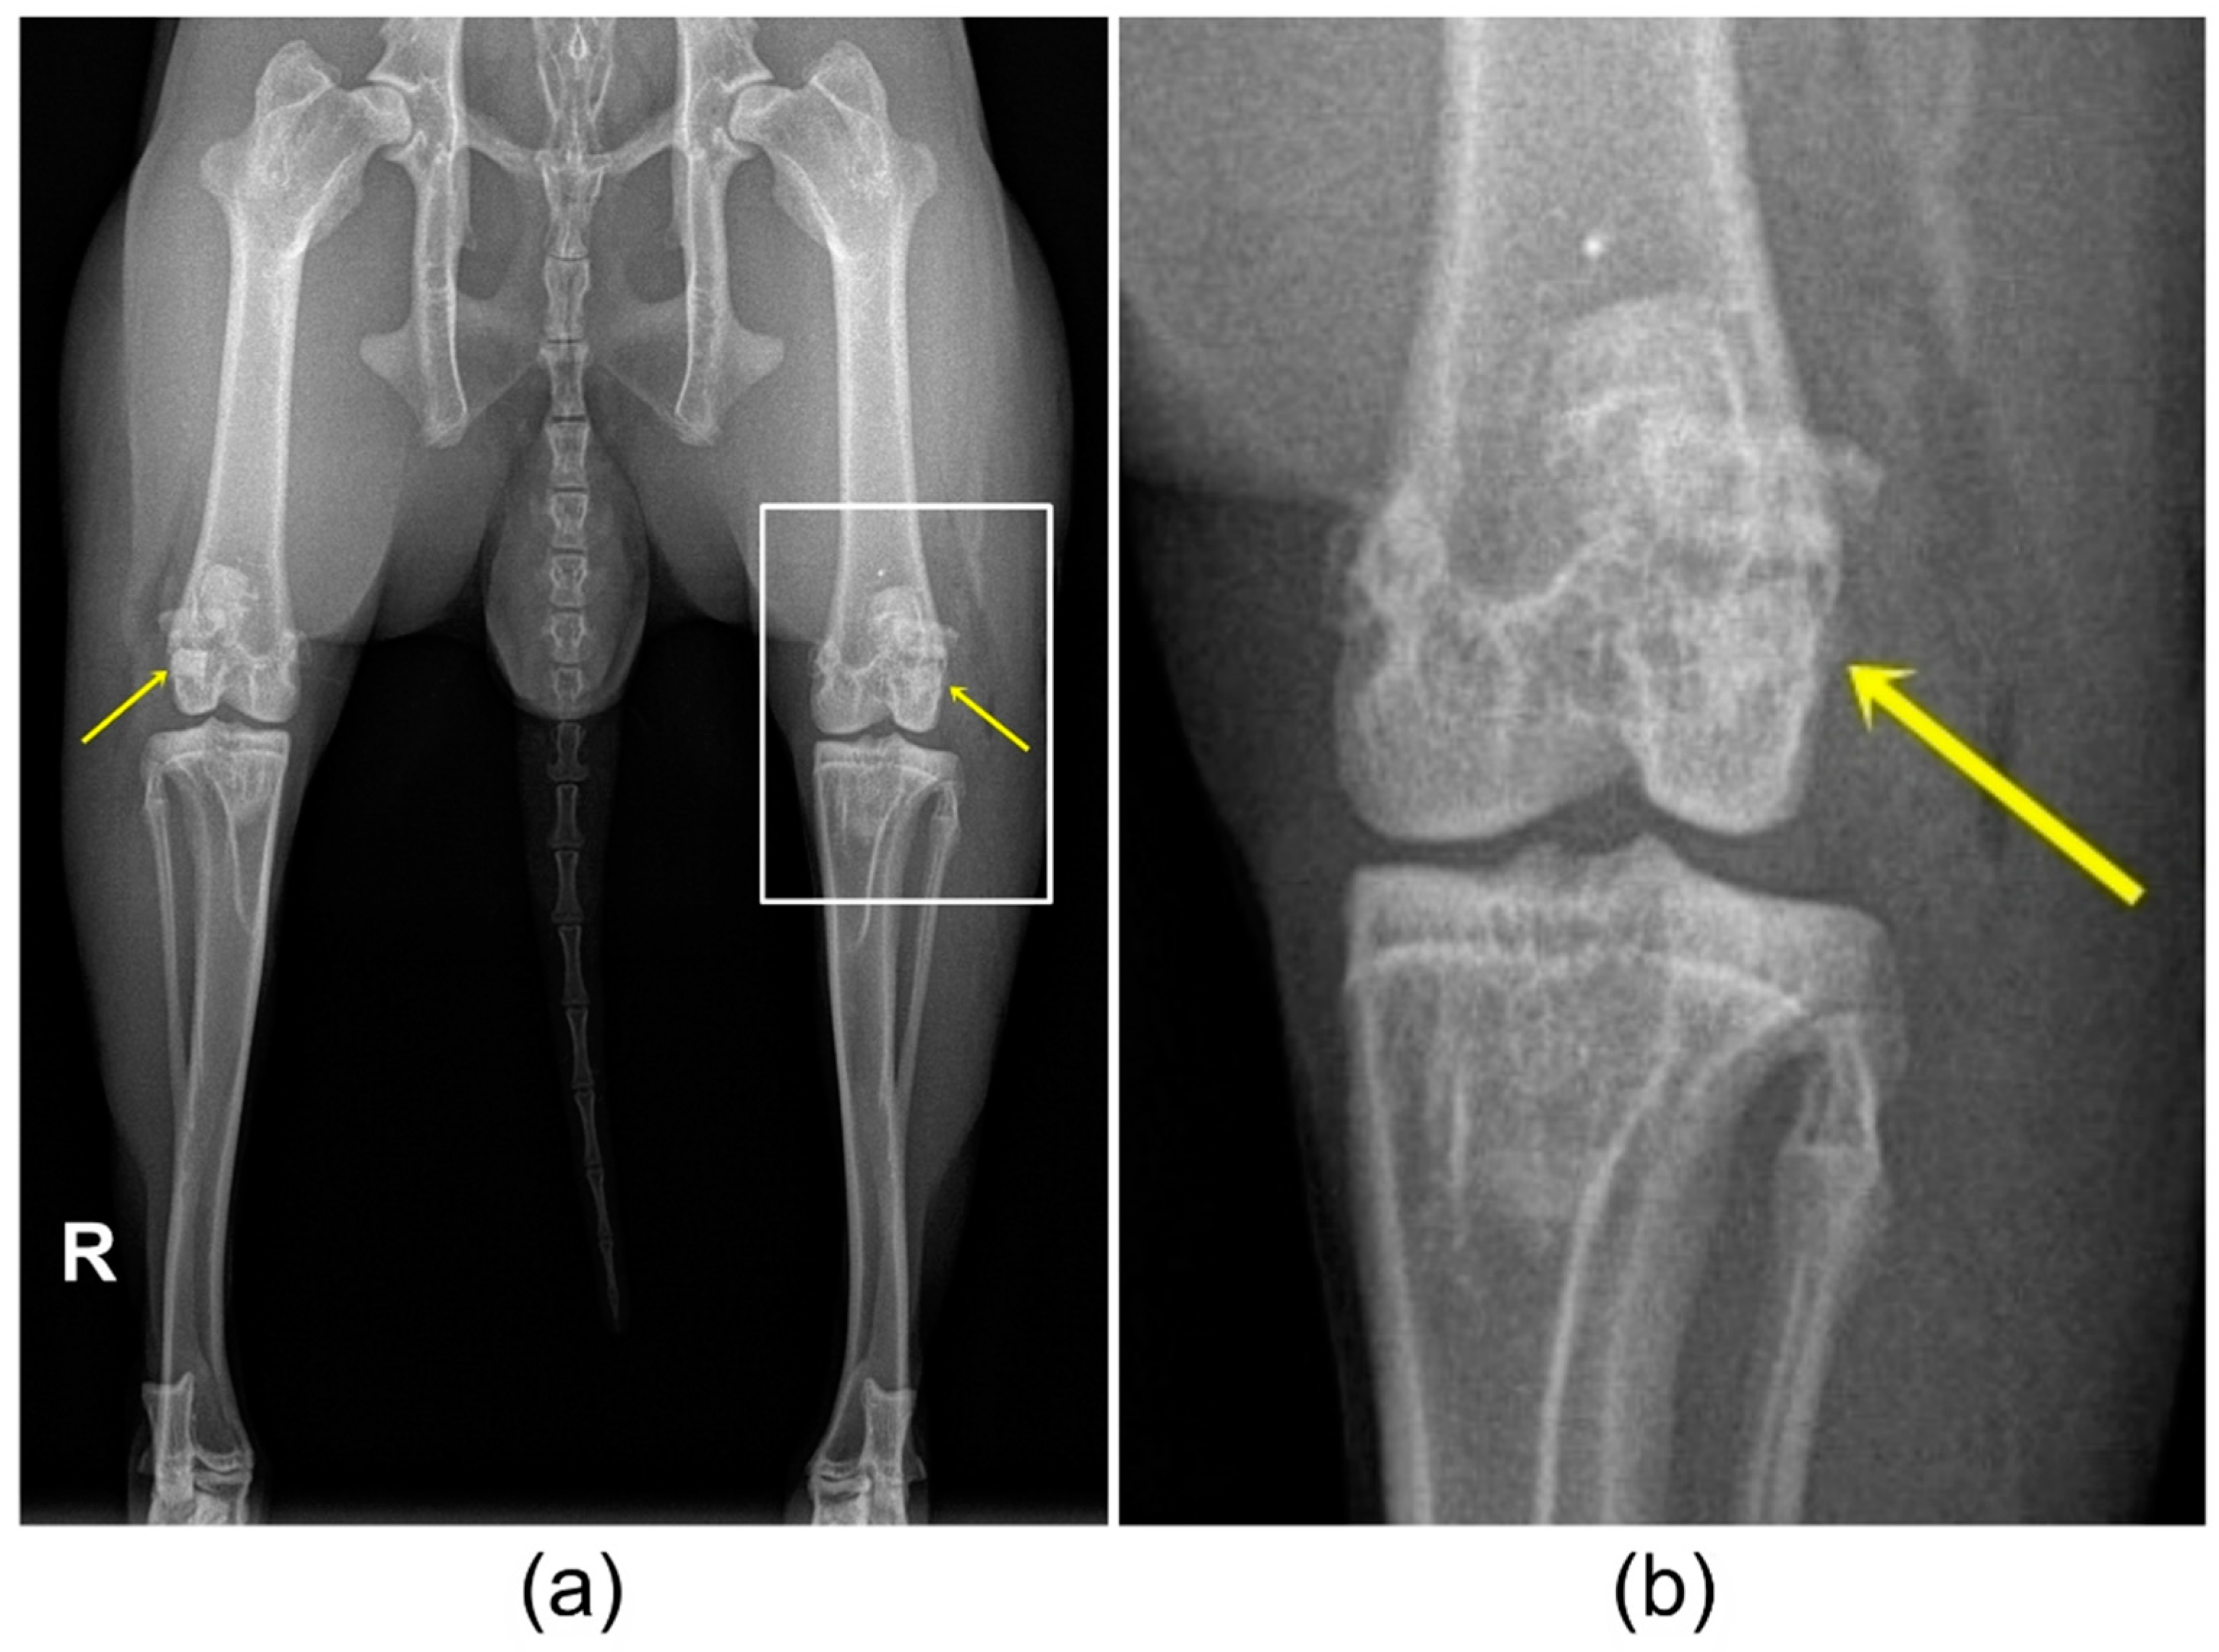

3.4. X-ray Examination

3.5. In-Vivo Micro-CT (µCT) Examination